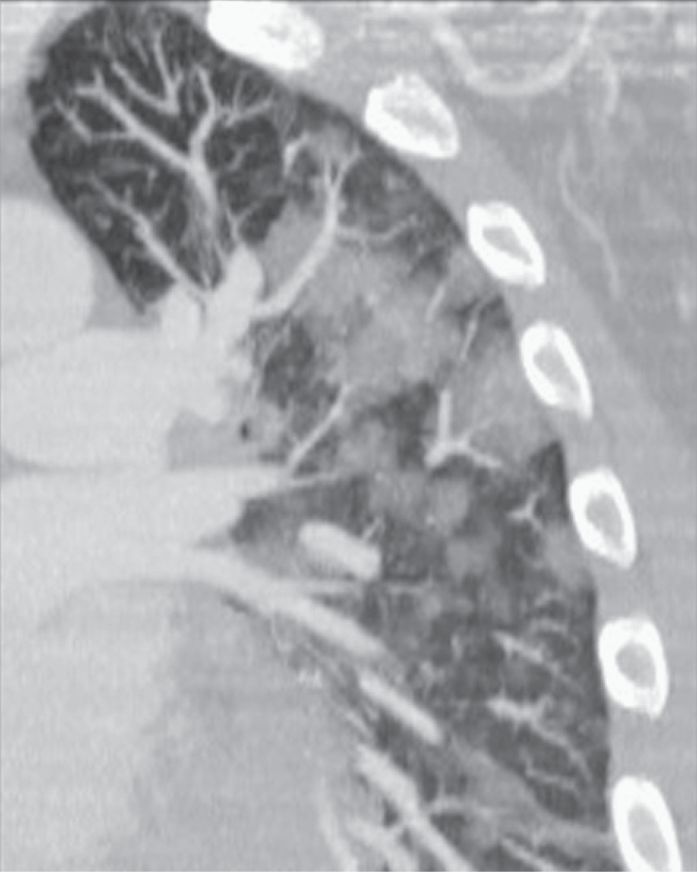

图2-4 实变,斑片状致密影

A、B. 支气管肺炎及小叶性实变患者增强HRCT显示单个小叶实变而周围邻近小叶正常,实变区小叶中心动脉( 白箭头) 和细支气管( 黑箭头);C. 冠状面CT 也显示斑片状实变影呈小叶性分布